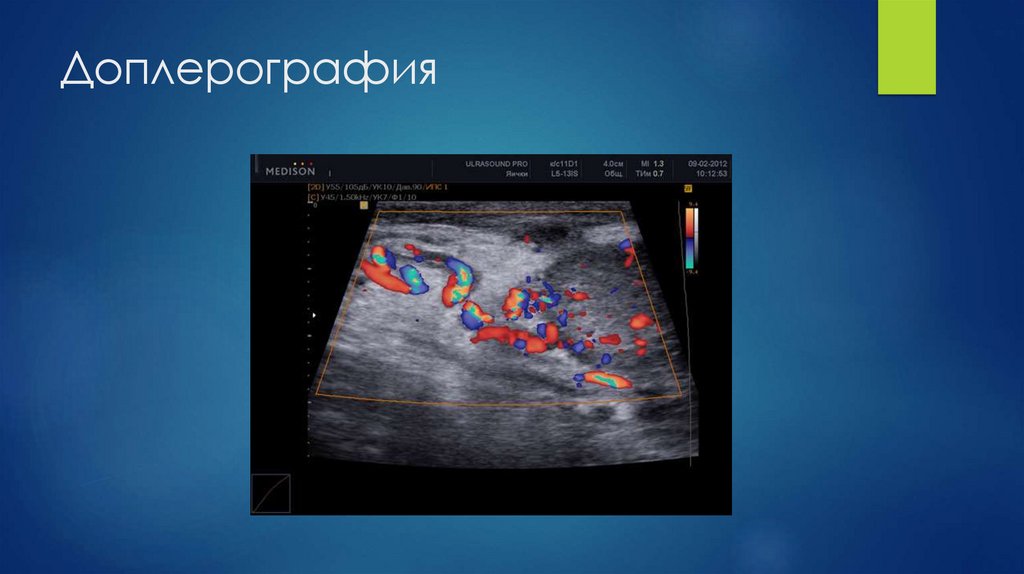

30. Доплерография